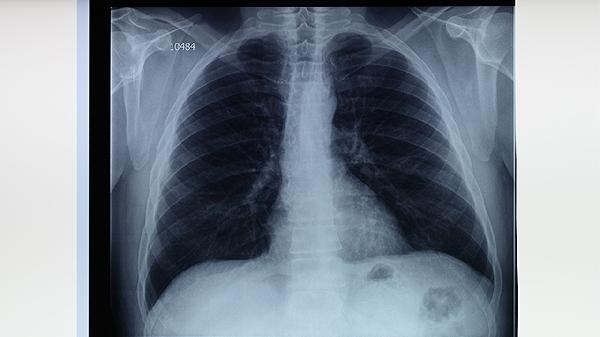

对高风险人群如密切接触者、免疫功能低下者、老年人等定期进行结核菌素试验或胸部X线检查。痰涂片和痰培养是确诊肺结核的主要方法,基因检测技术可快速识别耐药菌株。筛查阳性者需进一步评估活动性结核病风险,早发现可显著降低传播概率。